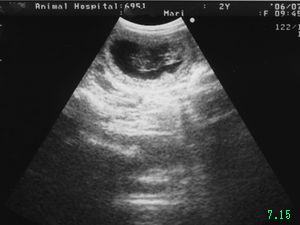

7月15日

交配後34日目

2度目のエコー検査を受ける為獣医さんへ

先ず体重を測り やはり2.6kgのまま。先生は普段より減っている体重を見て『う〜ん...減っちゃってるね』と渋い顔

一応エコーで見てみましょうとエコーを開始してくれ お父さんお母さんも一点のシミたりも逃すまいと真剣に画面を見つめます

2分位探しても何も映らず

『う〜ん...やっぱり無いねぇ。』

『......ん?あれ?あ〜?妊娠?(看護婦さんと顔を見合わせ) 妊娠してるね!こっちにもう1つ』

お母さんは思わずヤッター!と跳ね上がりました

エコーで2頭の胎児を確認 交配から1ヶ月余り、妊娠しているかどうか分からず気を揉んで過ごした日々の何と長く感じられた事でしょう

しかし先生からは妊娠したのに体重が減ってしまった事への懸念を指摘され 高栄養食のヒルズa/d缶を購入して帰宅しました